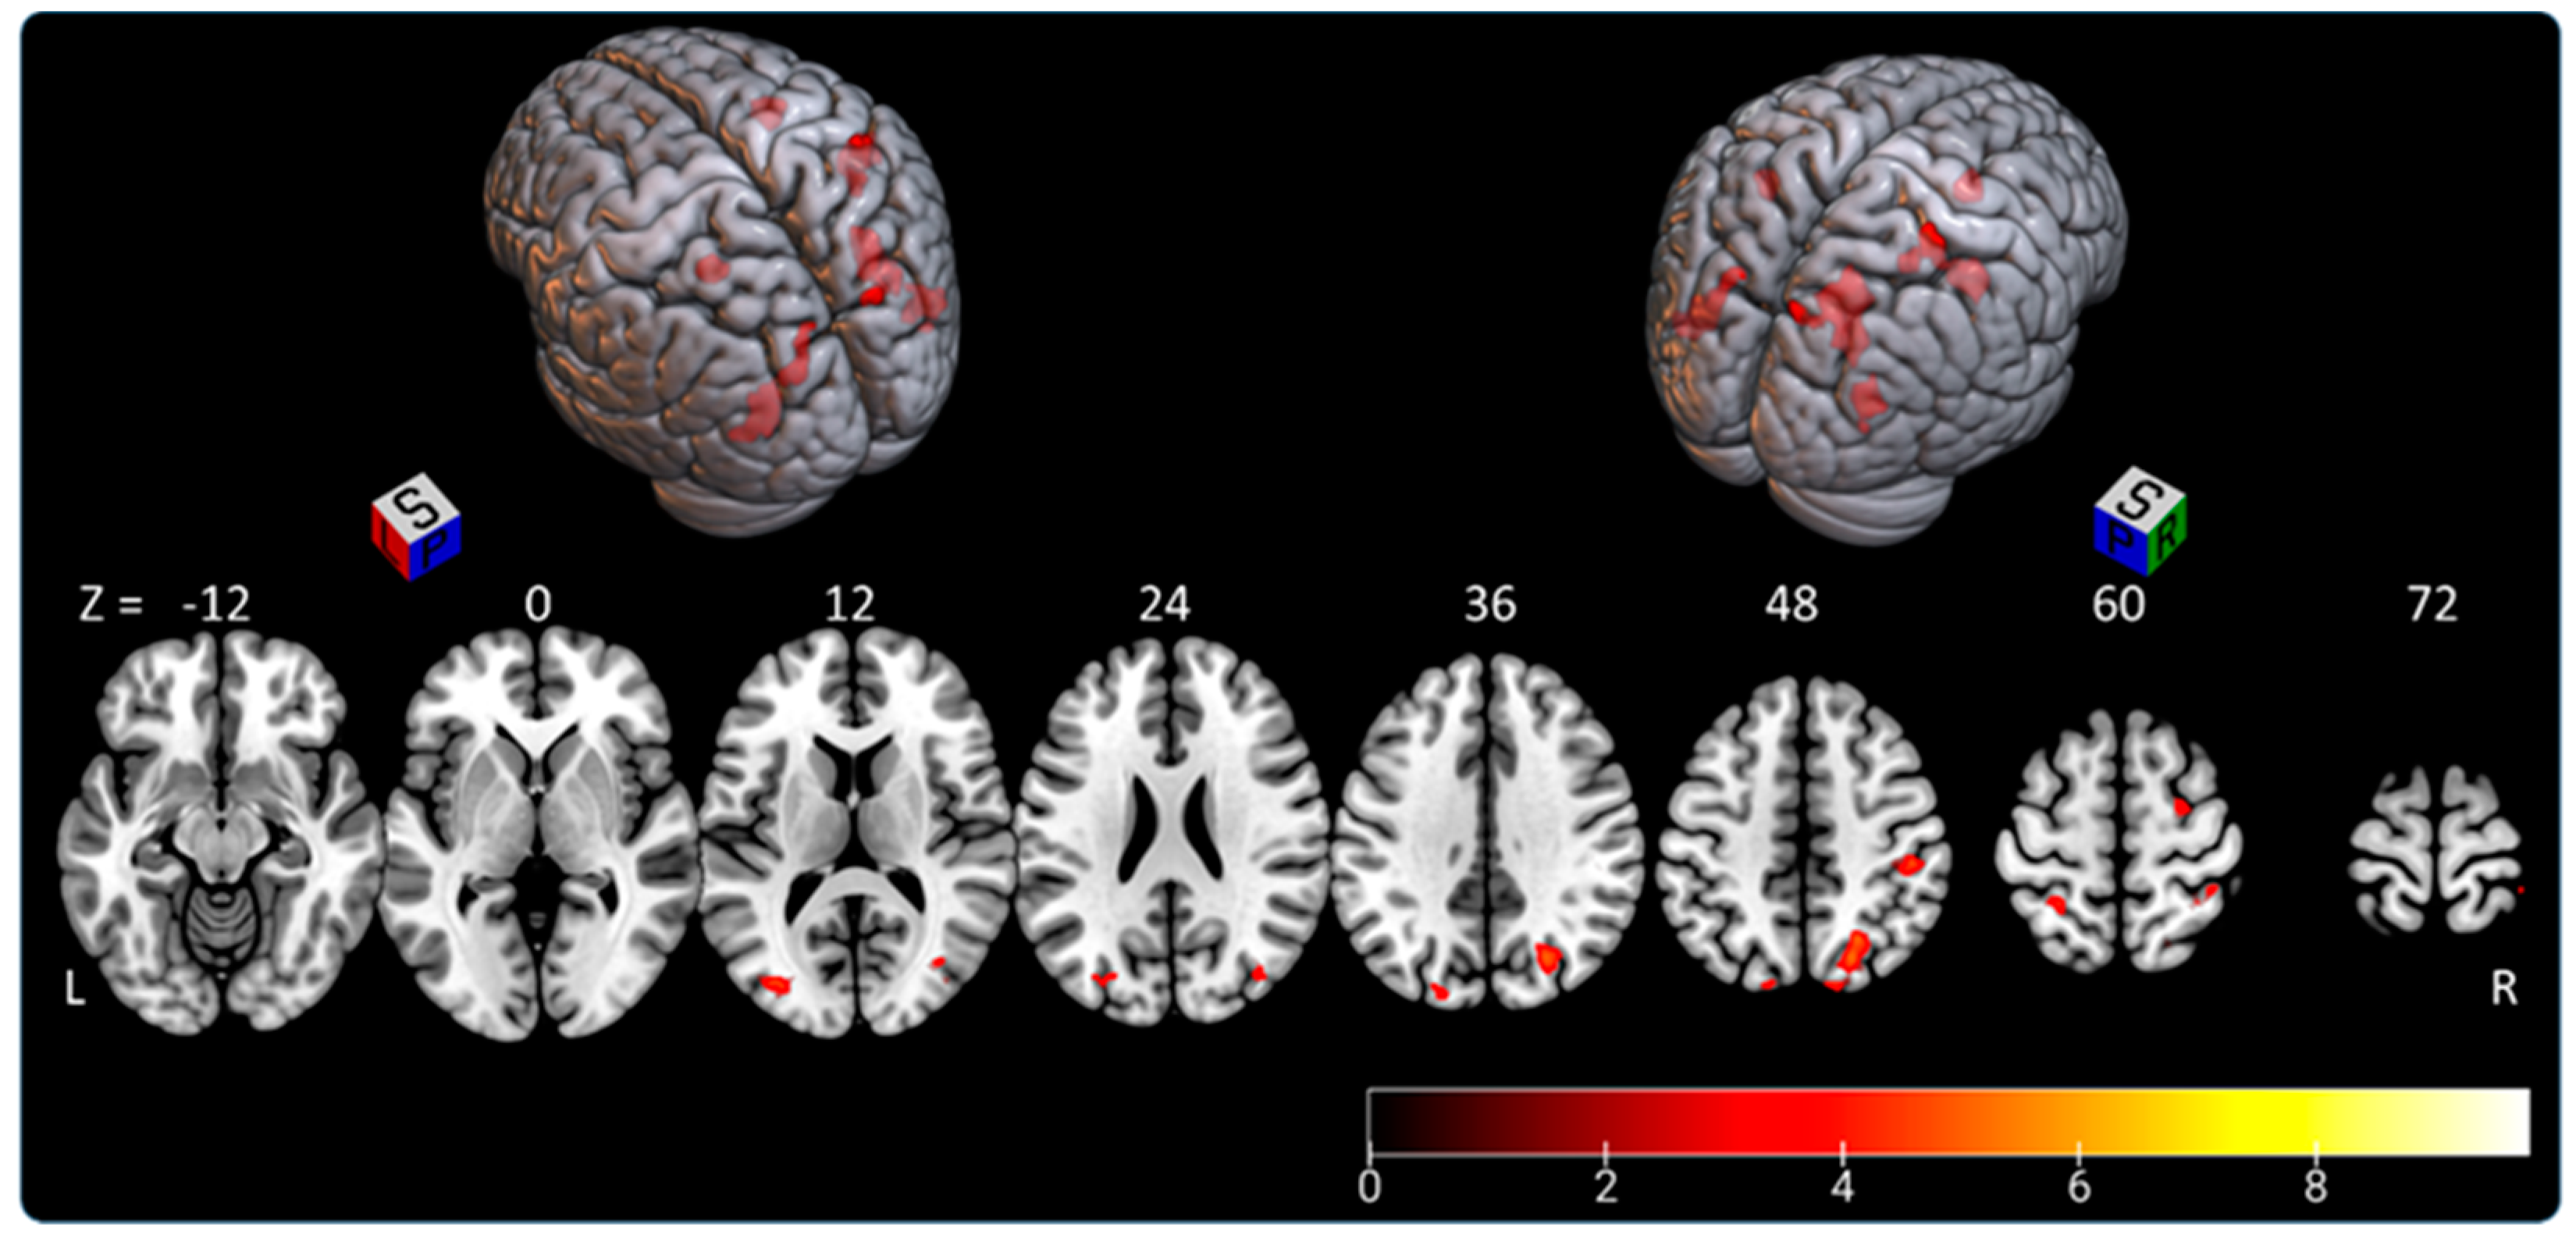

3.1. Subjective Straight-Ahead Task (SSA)

- the right parietal lobe (superior parietal lobule: A7c, A5l, A7pc; inferior parietal lobule: A39c, A40rd, A40rv; precuneus: dmPOS; postcentral gyrus: A2) representing 45.5% of activated areas;

- the right lateral occipital cortex (msOccG, lsOccG, mOccG), representing 21.5% of activated areas;

- the left lateral occipital cortex (V5/MT+, msOccG, lsOccG, mOccG), representing 16% of activated areas;

- the left parietal lobe (superior parietal lobule: A5l, A7pc; and inferior parietal lobule: A39c), representing 9.5% of activated areas; and

- the right premotor cortex (superior frontal gyrus: A6cdl), representing 7.5% of activated areas.

3.2. Subjective Longitudinal Body Plane Task (SLB)

- the right parietal lobe (superior parietal lobule: A7r, A7c, A5l, A7pc, A7ip; inferior parietal lobule: A39c, A40rd, A40rv; precuneus: dmPOS; postcentral gyrus: A1/2/3ulhf, A2, A1/2/3tru), representing 27% of activated areas;

- the right lateral occipital cortex (V5/M+, msOccG, lsOccG, mOccG, iOccG), representing 22.5% of activated areas;

- the right frontal lobe (predominant in the precentral gyrus: A4hf, A6cdl, A4ul, A4tl, A6cvl; superior frontal gyrus: A8m, A6dl, A6m; inferior frontal gyrus: A44d, A44op; paracentral gyrus: A4ll), representing 21% of activated areas;

- the left lateral occipital cortex (V5/MT+, mOccG, iOccG), representing 8% of activated areas;

- the left frontal lobe (supplementary motor area: A6m; precentral gyrus: A4hf, A6cdl, A4ul, A4t; and paracentral lobule: A4ll), representing 7.5% of activated areas; and

- less than 5% in each of the following areas: left parietal lobe (superior parietal lobule: A5l, A7pc; inferior parietal lobule: A39c, A39rv; postcentral gyrus: A1/2/3ulhf, A2), right insular lobe (vIa, dIa, dIg, dId), left temporal lobe (middle temporal gyrus: A37dl; inferior temporal gyrus: A37vl; fusiform gyrus: A37lv), left cingulate gyrus, right temporal lobe (middle temporal gyrus: A37dl; inferior temporal gyrus: A37vl; fusiform gyrus: A37lv), and right cingulate gyrus.

3.3. Subjective Longitudinal Body Plane Task versus Subjective Straight-Ahead Task